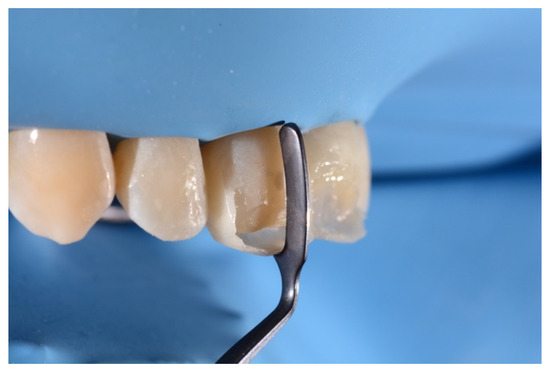

2. Case Presentation

- Building interproximal walls with matrices;